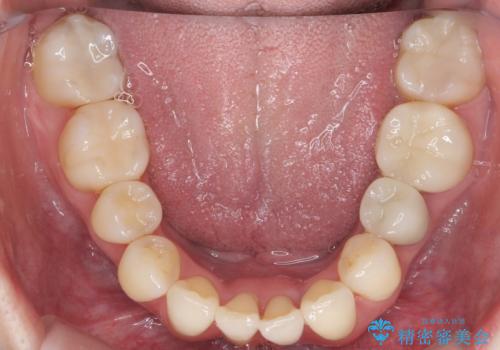

矯正治療後にしっかり全体の虫歯治療も行い、とても良い状態にできたと思います。

犬歯を抜いたとしても、矯正治療を短期間で終わらせて歯に負担がかからないようにし、虫歯治療その分しっかり行うのもメリットがあるのではないかと思います。

今回は特に左上の犬歯は歯肉退縮して根が露出していたのもあり、抜歯をお勧めしました。